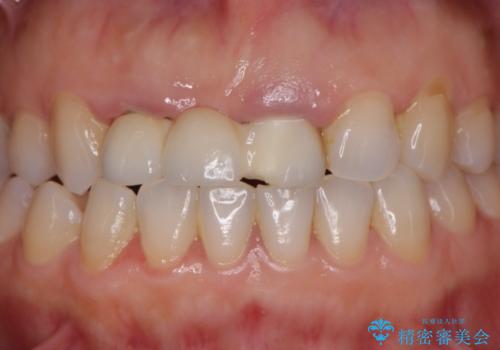

歯周外科をおこなったことで歯ぐきのラインを整え、脱離しないような前歯のブリッジを作製することができました。